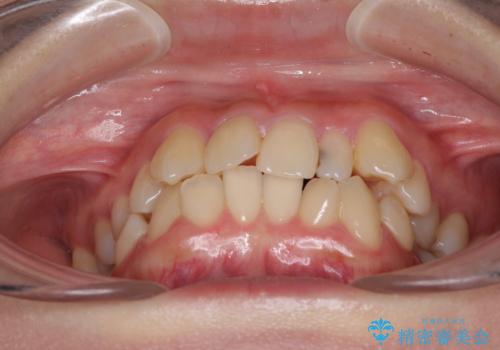

八重歯の抜歯矯正 補助装置を用いたインビザライン矯正

- 上顎の重なっている前歯を気にして来院された患者様です。

重なっている部分は抜歯が必要で、歯の移動量が多く、更には右側にずれている正中を改善する必要がありました。

インビザライン単体での治療は困難と判断し、補助装置により八重歯移動後にインビザラインを用いることとしました。

非常にしっかりとマウスピースを装着してくださいましたが、前歯の排列がなかなか仕上がらずに期間がかかってしまいました。